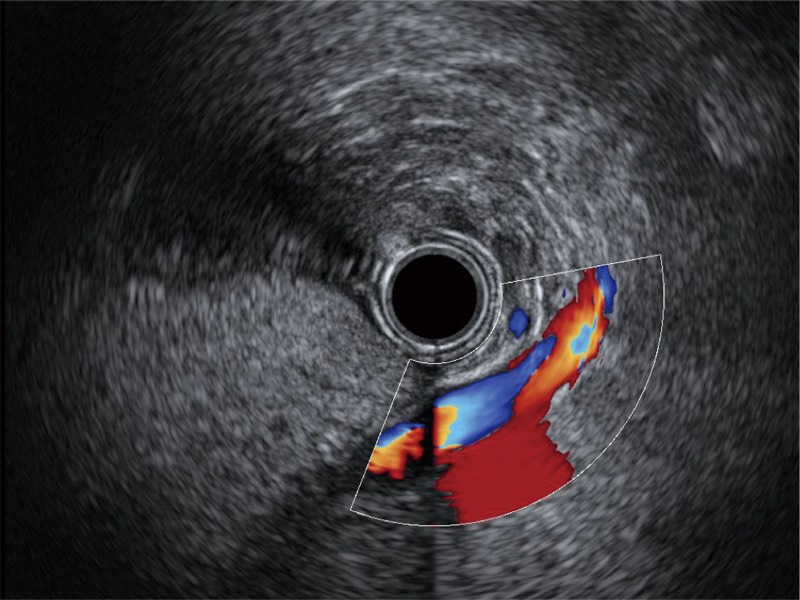

食管内间质瘤清晰显像

清晰显示胆总管及周围血管分布